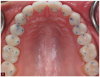

Fig 10. A preoperative study model was poured for evaluation and to guide placement of restorations to establish the ideal occlusion.

Figure 10